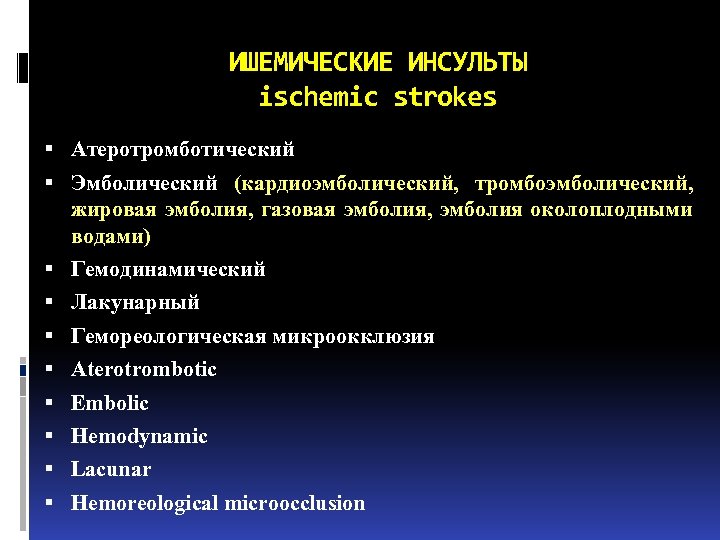

ИШЕМИЧЕСКИЕ ИНСУЛЬТЫ ischemic strokes Атеротромботический Эмболический (кардиоэмболический, тромбоэмболический, жировая эмболия, газовая эмболия, эмболия околоплодными водами) Гемодинамический Лакунарный Гемореологическая микроокклюзия Aterotrombotic Embolic Hemodynamic Lacunar Hemoreological microocclusion

ИШЕМИЧЕСКИЕ ИНСУЛЬТЫ ischemic strokes Атеротромботический Эмболический (кардиоэмболический, тромбоэмболический, жировая эмболия, газовая эмболия, эмболия околоплодными водами) Гемодинамический Лакунарный Гемореологическая микроокклюзия Aterotrombotic Embolic Hemodynamic Lacunar Hemoreological microocclusion